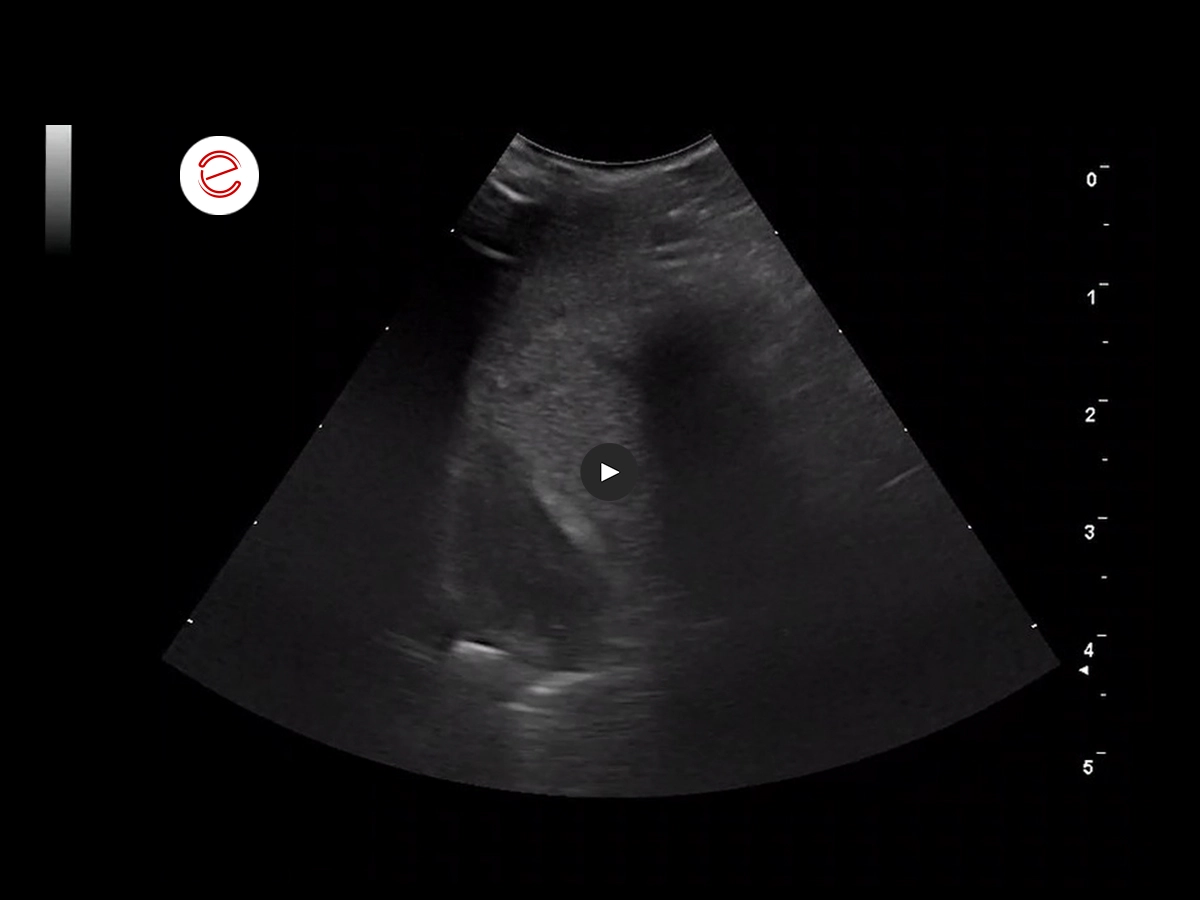

2 months before the respiratory issues: the larger right liver lobe is visible in the sagittal ventromedial view. The liver appears dense and heterogeneous, and the small hepatic vessels appear compressed.

The microV function outlines the compressed vessels.

Histopathology from an endoscopy-guided liver biopsy revealed liver fibrosis.

2 months later, the bird was presented for a follow up, mainly due to the sudden onset of respiratory problems.

There was a mild improvement of the liver.

Treatment: LIV52 (an ayurvedic remedy well established in avian medicine), Silymarin, Ursodeoxycholic Acid, dietary change.